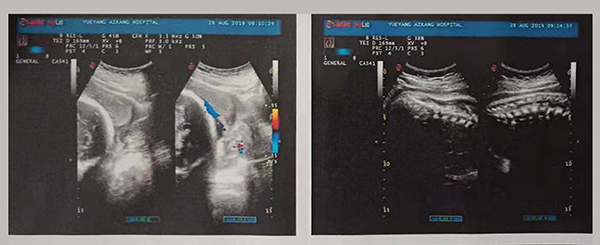

近日,岳陽愛康醫(yī)院產(chǎn)科團(tuán)隊(duì)成功搶救了一名完全性前置胎盤的產(chǎn)婦。完全性前置胎盤是妊娠期的嚴(yán)重并發(fā)癥,是分娩期子宮切除的一個(gè)重大高危因素之一,是引起孕產(chǎn)婦死亡和圍生兒死亡的重要原因之一。

2019年8月24日,易女士出現(xiàn)陰道流血,在岳陽縣人民醫(yī)院住院,住院期間予以安治、止血,于26日出院。28日早晨6點(diǎn)再次出現(xiàn)陰道流血,量多、顏色鮮紅、三片衛(wèi)生巾均浸透,遂來岳陽愛康醫(yī)院產(chǎn)科。

易女士一進(jìn)入病房就引起了岳陽愛康醫(yī)院產(chǎn)科主任高君萍的高度重視,考慮到手術(shù)的風(fēng)險(xiǎn)大,手術(shù)過程復(fù)雜,有可能出現(xiàn)新生兒窒息、產(chǎn)婦大出血等危及母嬰生命的并發(fā)癥,甚至切除子宮可能。在檢驗(yàn)科充分術(shù)前配血、血漿的準(zhǔn)備及全院MDT(多學(xué)科聯(lián)合會診),立即進(jìn)行手術(shù)。

術(shù)中,擺在產(chǎn)科團(tuán)隊(duì)面前的第一個(gè)嚴(yán)峻考驗(yàn)出現(xiàn)了,整個(gè)子宮下段前壁膨隆血管怒張!迅速設(shè)計(jì)子宮切口,取出胎兒,面臨又一嚴(yán)峻的考驗(yàn),胎盤大面積植入整個(gè)子宮下段前后壁,迅速行雙側(cè)子宮動脈下行支結(jié)扎,迅速人工剝離胎盤以及卵圓鉗鉗夾剩余胎盤組織,植入的胎盤處理干凈后子宮下段前后壁多處肌層缺損伴有大量活動性出血,迅速行子宮下段整形修復(fù)縫合止血……不得不說產(chǎn)婦是幸運(yùn)的,婦產(chǎn)科、手術(shù)麻醉科等多科通力合作,經(jīng)過約2小時(shí)的手術(shù)及搶救止血,術(shù)中共計(jì)出血1500ml,輸懸浮紅細(xì)胞4個(gè)單位,終于保得母女平安,并完美的保留了子宮。易女士術(shù)后恢復(fù)良好,對婦產(chǎn)科的精湛技術(shù)贊不絕口!